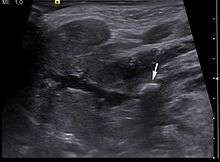

Diagnosis is usually made by characteristic history and physical examination. Diagnosis can be confirmed by x-ray (80% of salivary gland calculi are visible on x-ray), or by sialogram or ultrasound.